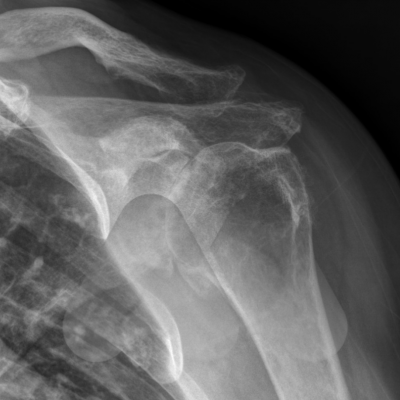

The first step is to confirm the diagnosis with an examination from your doctor and plain x-rays.

Shoulder arthritis can develop in two main patterns, one where there is no known cause and secondly can be as a long term consequence of a torn rotator cuff resulting in rotator cuff arthropathy.

It can lead to pain, stiffness and sometimes a “creaking” or “crunching” in the movements of the shoulder.